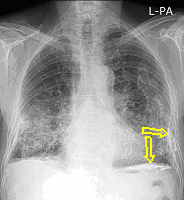

23. Pulmonary metastases, bidirectional (PA and right lateral) plain chest radiograph.

51 year old woman, endometrial carcinoma. Numerous ring shadows bilaterally in basal dominance (max. appr. 12 mm). Left pleural effusion of one finger wide.